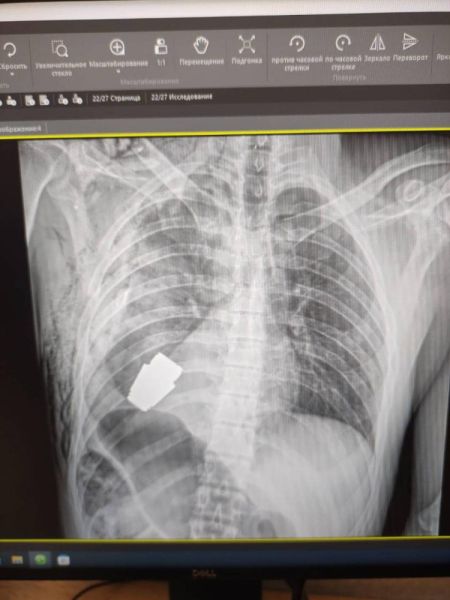

Військові лікарі провели унікальну операцію. Медикам вдалося безпечно витягнути з тіла українського захисника гранату ВОГ.

Боєприпас довелося вилучати в присутності двох саперів, які відповідали за безпеку медичного персоналу.

«Операція проводилася одним з найдосвідченіших хірургів ЗСУ – Андрієм Вербою без електрокоагуляції, оскільки граната могла детонувати у будь-який момент», – розповіла Ганна Маляр.

На щастя, операція пройшла успішно. На пораненого військового чекає реабілітація та подальше відновлення.